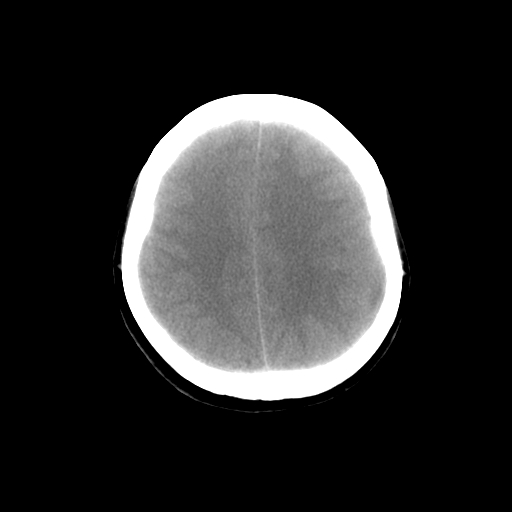

标题: CT14513:女性41岁,头部不适二月余,其它病史不详。请分析 [打印本页]

标题: CT14513:女性41岁,头部不适二月余,其它病史不详。请分析

1.考虑:左侧颞顶叶星形细胞瘤。2.大脑镰下疝。

支持!但楼主所提示处颅骨明显受压变薄,是否有合并蛛网膜囊肿或局部硬膜下水瘤的可能?脑穿通畸形暂不予以考虑:明显占位表现;病侧脑室无扩张;病灶不是较明确的脑脊液密度;边界不清晰。还是mri检查吧,提供的有价值信息更多一些,至少可以排除或肯定蛛网膜囊肿或局部硬膜下水瘤的存在。

1)考虑左侧颞顶叶胶质瘤。2)左侧颞顶部慢性硬膜下血肿?3)大脑镰下疝。